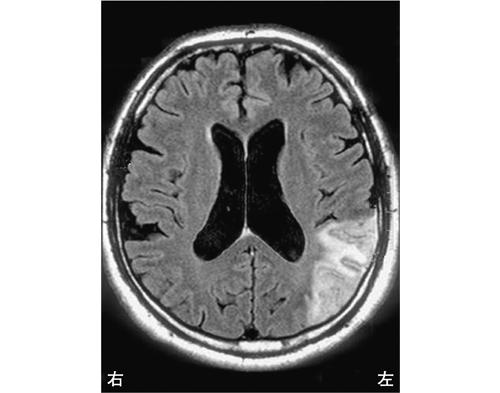

左前頭葉では非流暢性失語が見られるため、この選択肢は誤りです。左半側空間無視は、右頭頂葉後部で見られる症状です。

左放線冠は部位によって様々な症状が現れますが、感覚性失語はWernicke領域で見られるため、この選択肢は誤りです。